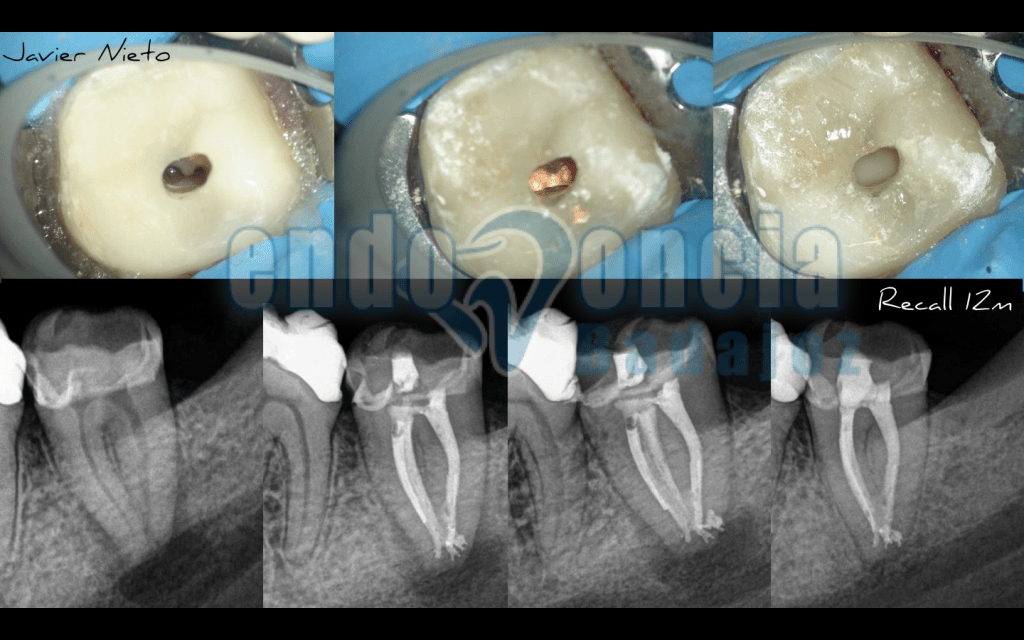

Anatomía de un 3.7

Subimos este casito de un 3.7, en el que intentamos ser lo más conservador posible, y que realmente, nos habría gustado que estéticamente fuese más bonito, pero que finalmente quedó tal y como veis. Comparto la opinión de que se trata de casos mucho más complicados y que pueden hacer que si no estudiamos bien el caso, puede que fracasemos por no tratar la anatomía de la mejor manera.

Al año, vemos el resultado de un tratamiento predecible.